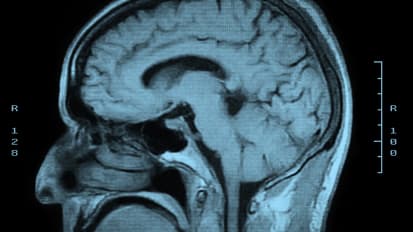

Dr. Grabowski is a UW professor of radiology and joint professor of neurology. He is a neurologist and an expert on the diagnosis and treatment of conditions affecting memory, language and cognition. He is the director of the UW Medicine Memory and Brain Wellness Center. He is also a cognitive neuroscientist who directs the UW Integrated Brain Imaging Center, dedicated to investigating the organization of the brain and the basis of cognition using MRI imaging approaches.